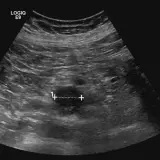

Casos totalmente interativos com as ferramentas que você espera em um PACS — rolagem, ajuste de janela, zoom, movimentação, medidas, ROIs e modo de tela cheia.

Anotações detalhadas destacam os achados principais diretamente nos casos. Clique nos achados vinculados nas descrições dos casos para ir ao local exato no exame.